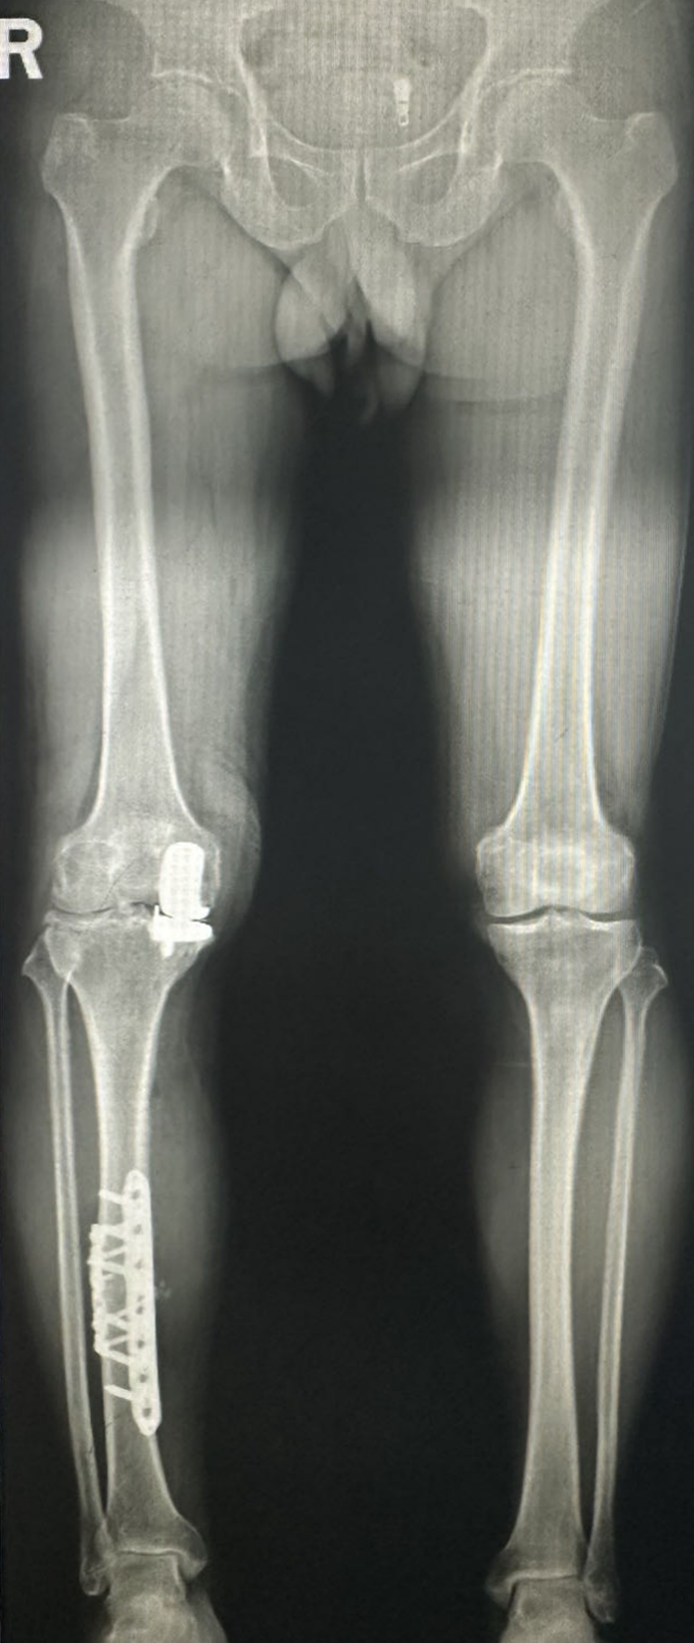

术后

4月4日,在董孟政主任医师团队的努力下手术顺利完成,患者恢复良好。

术后患者的骨折畸形不仅得到纠正,膝关节疼痛也得到了明显缓解,现患者已顺利出院,随访患者定期来院复查,了解骨折愈合情况。